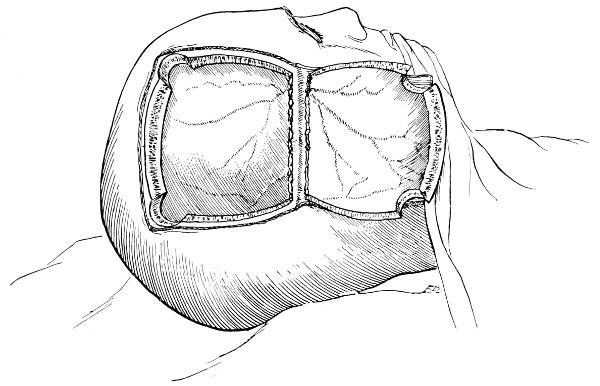

Fig. 18. Second Stage in the Formation of an Osteoplastic Flap. The bone-flap turned down and the dura mater exposed.

Fig. 19. Third Stage in the Formation of an Osteoplastic Flap. The dural flap turned down and the brain exposed. Note the relation of the scalp, bone, and dural incisions to one another.

Reference has already been made to the great importance of opening the dura in such a manner as to avoid injury to the underlying superficial cerebral vessels (see p. 19). It may be incised in a crucial manner or by flap-formation. Flaps are usually to be preferred if the surgeon desires to have the widest possible view of the brain surface. In the formation of the flap, advantage should be taken of the vessels that minister to its vitality. Thus, in the lateral region of the head, the base lies below, the middle meningeal artery supplying the flap. Under special circumstances, the blood-supply may be disregarded; the flap never sloughs, so far as my experience goes.